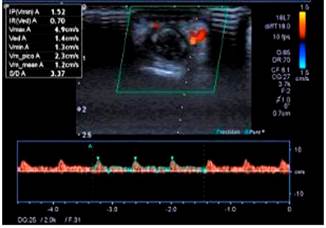

48 horas después del procedimiento endoscópico presentó lesiones dérmicas petequiales y necróticas en el cuarto dedo de la mano izquierda (Figuras 6 y 7), por lo que se le realizó una ecografía Doppler de miembro superior en la que se encontraron fluidos disminuidos con ondas parvus tardus en las arterias digitales palmares y dorsales del cuarto dedo de la mano izquierda (Figura 8). Fue valorado por dermatología y se realizó la toma de biopsia que dio como resultado vasculitis de pequeños vasos (paniculitis septal, infiltrado inflamatorio perivascular con predominio de neutrófilos, daño fibrinoide y hematíes extravasados). Recibió tratamiento de 3 pulsos de metilprednisolona 500 mg intravenoso, que posteriormente pasó a ser por vía oral con prednisona 60 mg hasta decalar y se retiró el corticoide; posteriormente se administró metronidazol 500 mg intravenoso por 14 días y mesalazina 3 g por vía oral hasta el momento. Actualmente, el paciente se mantiene asintomático sin signos de lesiones en las manos ni la lengua, y en remisión clínica de la CU, sin uso de corticoides, con mesalazina 3 g/día y tiene controles en consulta externa sin manifestaciones clínicas.